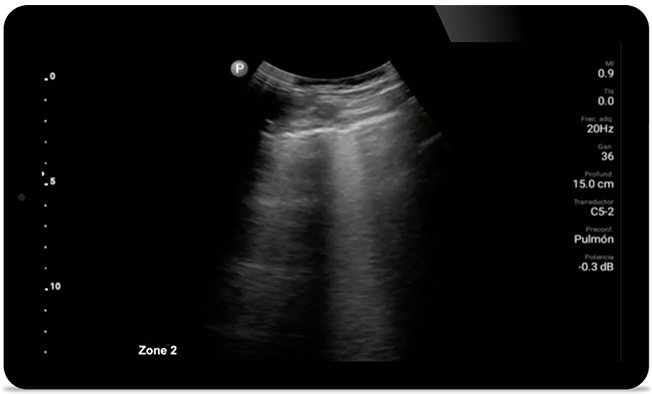

Lepsza kontrola zapalenia płuc w przebiegu COVID

W przypadku oceny zapalenia płuc oraz zespołu niewydolności oddechowej u osób dorosłych system Lumify pozwala uzyskać obrazy o jakości niemal analogicznej do obrazów TK klatki piersiowej.